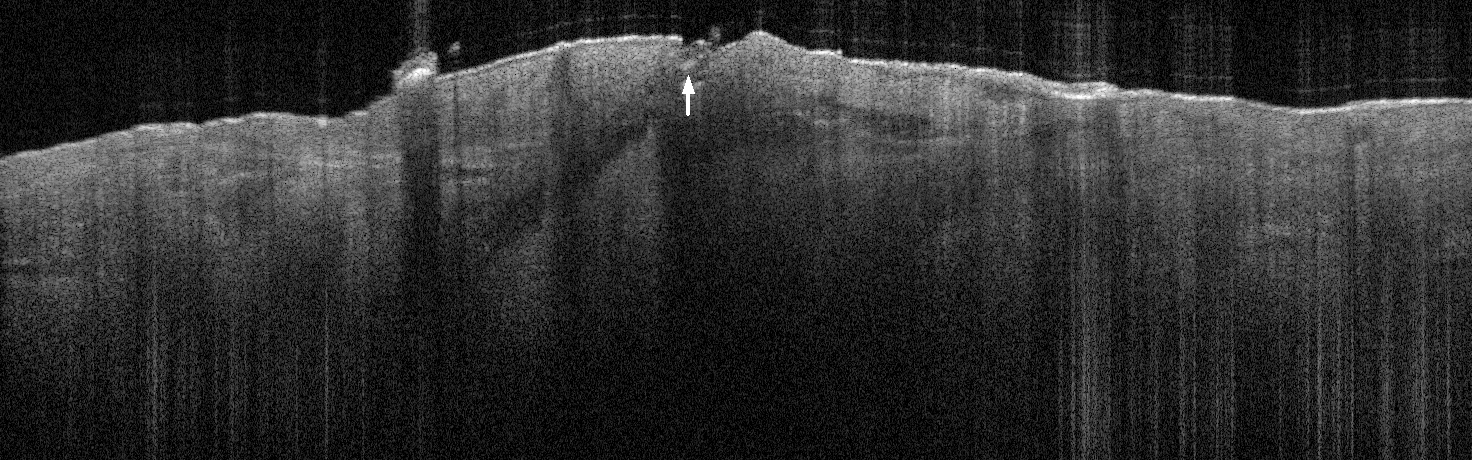

VA34: Right Temple, Actinic Keratosis, Hypotrophic, Focally reaching the base.

- White arrow denotes hair follicle